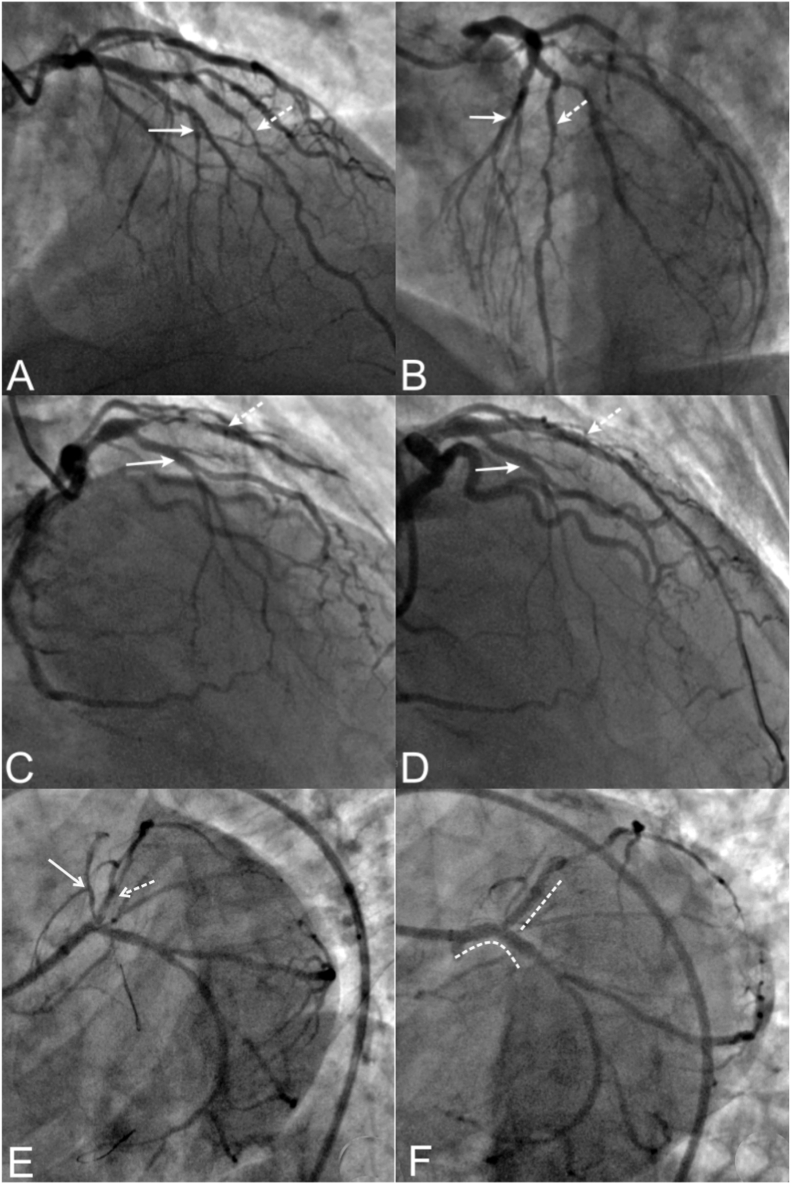

Fig. 4.

Coronary angiography of three illustrated cases form our institute demonstrating group I-A dual LAD. Case 1 (Panels A, B): Right anterior and left anterior oblique views revealed the Left main coronary artery bifurcated into the left anterior descending artery (LAD) and left circumflex artery (LCX). The LAD proper is divided into the LAD1 and LAD2. The LAD2 and LCX had significant atherosclerotic stenoses. The 1st diagonal branch also a significant lesion of its ostio-proximal segment which arose from the LAD1. LAD2 also gave rise to retrograde collateral (Rentrop grade 3) to the critically stenosed right coronary artery territory [Not shown]. The patient underwent coronary artery bypass surgery due to symptoms of effort angina and underlying triple vessel disease. Case 2 (Panels C, D): Right anterior oblique views demonstrated critical stenosis of the proximal segment of the LAD2 with thrombolysis in myocardial infarction (TIMI) II flow. LAD1 and other arteries were normal. Percutaneous coronary intervention with a drug-eluting stent could restore TIMI III flow and alleviate his symptom of exertion-induced angina. Case 3 (Panels E, F): Left anterior caudal view demonstrated separate origin of the LAD1 and LAD2 from the LMCA. The LAD1 was misinterpreted for the proper LAD and LAD2 was misinterpreted as a ramus intermidius branch. There was a significant stenoses of the ostio-proximal segments of LAD1, LAD2 and LCx. Patient underwent percutaneous coronary intervention of the LMCA using two stent strategy.